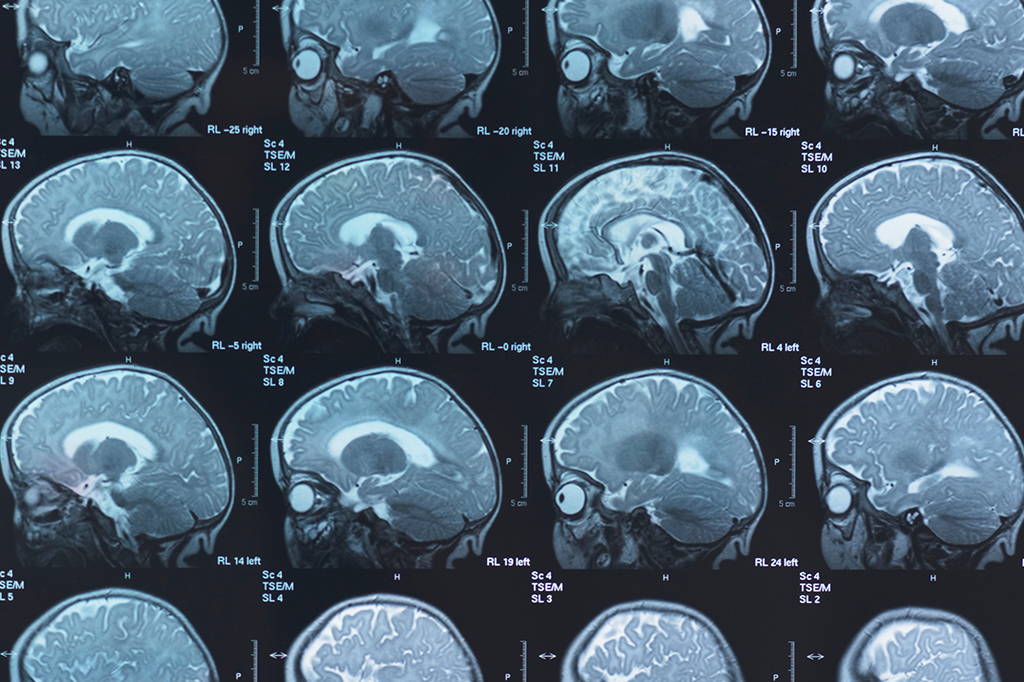

Essa discrepância surge no início da vida adulta e permanece inalterada com o passar dos anos, até a velhice. Para fazer essa análise, os cientistas usaram a técnica da tomografia por emissão de pósitrons a fim de avaliar o fluxo de oxigênio e glicose nos cérebros de 121 mulheres e 84 homens, com idades entre 20 e 82 anos.

Exames como o utilizado no estudo permitem mensurar o nível de um processo chamado glicólise aeróbica, muito intenso no desenvolvimento cerebral de bebês e crianças. Ele vai diminuindo com o tempo até se estabilizar em níveis bem baixos, após os 60 anos. Para definir as diferenças entre os sexos, os pesquisadores elaboraram um algoritmo que classifica a idade das pessoas com base nos resultados nas análises cerebrais.